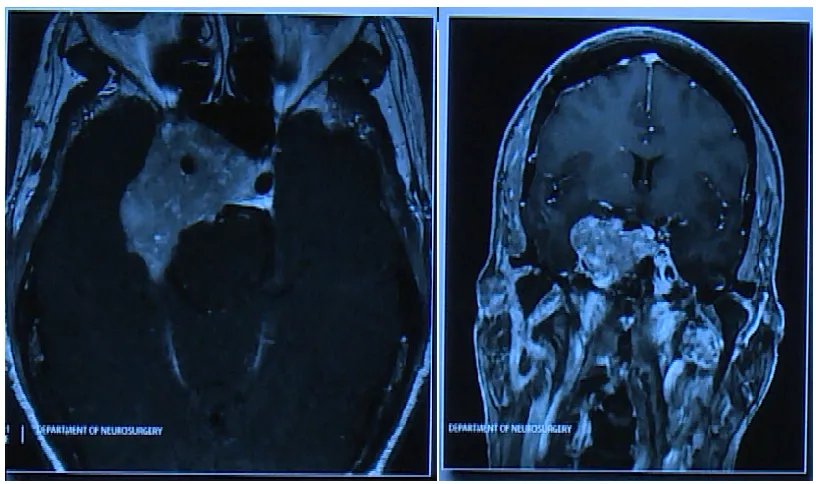

45岁这一年,患者的生活被脑干内破裂的海绵状血管瘤彻底改变。起初认为这种良性血管瘤无需过度担忧,至少不会引发严重出血。但当患者卧床不起,身体半侧瘫痪,面部歪斜时,才真正意识到问...

虽然听神经瘤属良性病变,但由于肿瘤位置深在、毗邻脑干,且与面神经粘连紧密,手术治疗不仅难以保留听力功能,面神经麻痹的发生风险也极高。因此,医生初步推荐保守治疗或放射治疗方案...

声音嘶哑可能作为肿瘤预警信号存在。33岁男性患者遭遇巨大脊索瘤侵蚀颅骨并压迫脑干,临床表现为声音嘶哑、舌部麻木等症状。脊索瘤属于罕见的高度侵袭性骨恶性肿瘤,虽部分生长缓慢但仍具...

"原以为是颈椎劳损"。病情在24小时内急剧恶化:从颈部酸痛发展为剧烈呕吐,最终在救护车上失去颈部以下所有知觉。急诊初步诊断为脊髓血管病变,住院11天期间左侧躯体部分恢复知觉,但右侧...

52岁女性患者金女士,既往身体健康。2021年因心脏不适症状就诊,在进行心脑血管系统检查时,意外发现脑干区域存在海绵状血管瘤病变。该病变位于脑干这一重要功能区,负责调节呼吸、心跳等...

小学二年级学生主诉头痛症状,在家长准备驾车送医过程中出现呕吐症状。抵达医院后,CT检查显示严重脑干出血征象,医生立即建议转诊至上级医疗机构。患儿病情迅速恶化,救护车转运途中已出...

"巴特朗菲教授您好,我现在恢复得相当不错!"这段来自丘脑海绵状血管瘤患者文文的康复视频中,她行动自如,言语间表情生动,完全看不出三个月前刚经历高难度脑部手术的痕迹。这种充满生命...